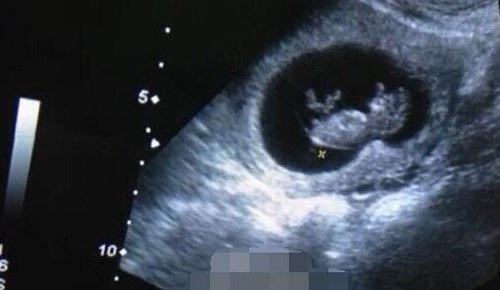

欧弟女儿B超照

去年8月,欧弟与重庆妹子郑云灿在重庆领证结婚,今年5月在捷克举办浪漫婚礼,婚后受访时就表态称希望尽快生个当爸爸。今年6月17日,欧弟透过微博发布一张孕妇B超照片,宣布与妻子造人成功,即将当爹。